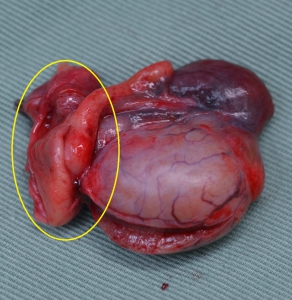

まず、精巣や精巣上体、それを取り巻く血管や精管がどのような構造と位置関係なのかを下の写真でご覧になってください。精巣(黄色星印)でくつくり出された精子は副睾丸とも呼ばれる精巣上体(グリーン丸印)へと輸送されて貯蔵され、さらに精管(青矢印)を通って体内に運ばれます。

下の写真が精巣・精巣上体炎を起こした犬の精巣上体を黄色丸印で示しています。右が正常、左が精巣上体炎の見られた睾丸です。2週間程度の抗生物質による治療後にも痛みと腫れが残ったため、症状の緩和のために去勢手術を実施したものです。当初の著しい腫れは見られませんが、全体的にかなり赤みを帯びており、精巣上体は明らかに硬い印象がみられました。